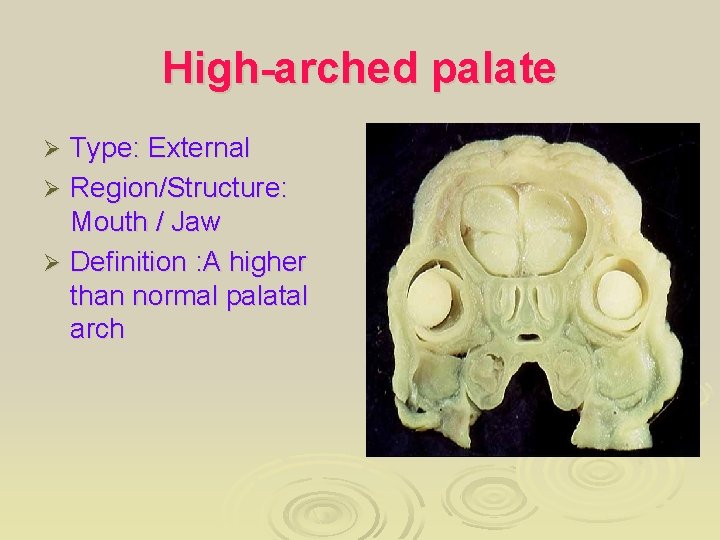

High-arched palate Type: External Ø Region/Structure: Mouth / Jaw Ø Definition : A higher than normal palatal arch Ø